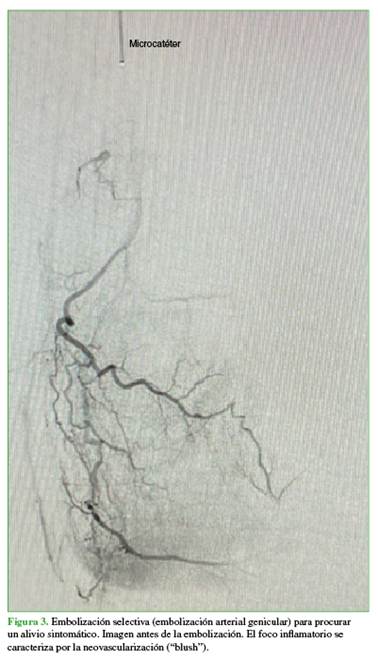

Se le propone la embolización arterial selectiva (Figura 2).

El paciente refiere franco alivio sintomático tras la embolización (Figura 3).

La técnica consiste en la embolización superselectiva de ramas arteriales geniculares que irrigan áreas de neoangiogénesis sinovial, buscando una reducción controlada —aunque no la oclusión completa— del flujo hacia los vasos patológicos, con el objetivo de disminuir la inflamación y el dolor, minimizando, a su vez, el riesgo de isquemia en tejidos vecinos (Figura 4).13